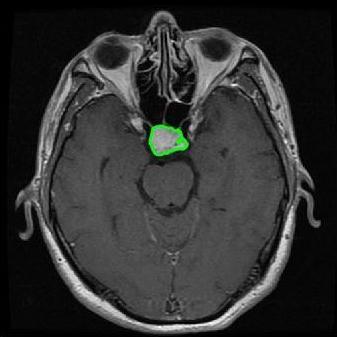

From the above discussions, we have discovered the significant potential of applying Retinex theory to image segmentation and explored its fundamental differences from traditional models. Traditional image segmentation models typically focus on the impact of intensity information on the segmentation results. Therefore, when faced with complex segmentation scenarios, the segmentation results are often affected by lighting, artifacts, and unclear boundaries in the image. As shown in Fig. 1, we present the results of the classical local model LIF [ZHANG20101199] for segmenting brain tumor images along with surrounding tissue edema. The irregular ring-like enhancement caused by the edematous tissue leads to irregular boundaries and low contrast in the images. Consequently, the LIF model can only identify the central necrotic and liquefied regions of the tumor, failing to detect the boundaries and becoming trapped in local minima. In this paper, we draw inspiration from the Retinex theory, which is widely applied in the field of image enhancement. According to Retinex theory, the reflectance component characterizes the intrinsic structural properties of the observed image and preserves texture information independent of illumination variations. By integrating this reflectance component into the level set framework, our model achieves robust segmentation of medical images even under severe intensity inhomogeneity. In addition, a linearized Structural-Prior is proposed to restore intensity consistency and capture local geometric features, thereby improving boundary localization in complex or blurred regions. Furthermore, a relaxed binary level set representation is employed to enhance robustness against noise and to enable accurate tracking of complex contours. Based on these innovations, we propose a novel variational reflectance-based level set model (RefLSM) that simultaneously corrects bias fields and performs segmentation. Experimental results demonstrate that RefLSM significantly outperforms conventional level set methods in both segmentation accuracy and robustness. We present the results of our model segmenting the two brain tumor images mentioned above in Fig. 2.

To address the challenge of segmenting images with severe intensity inhomogeneity, we propose a linearized structural prior that directly operates on the reflectance component . Reflectance-based structural information is more robust to illumination variations and bias field distortions, helping preserve weak edges and subtle anatomical boundaries. As shown in Fig. 2, our method can accurately delineate tumor boundaries and surrounding edema even under severe inhomogeneity, where traditional intensity-based models often fail. The proposed prior aligns smoothed reflectance gradients with data-driven directions, enhancing inter-region contrast, preserving weak edges, and stabilizing the evolution of . Formally, we define the linear structure operator as the gradient field of the smoothed reflectance: